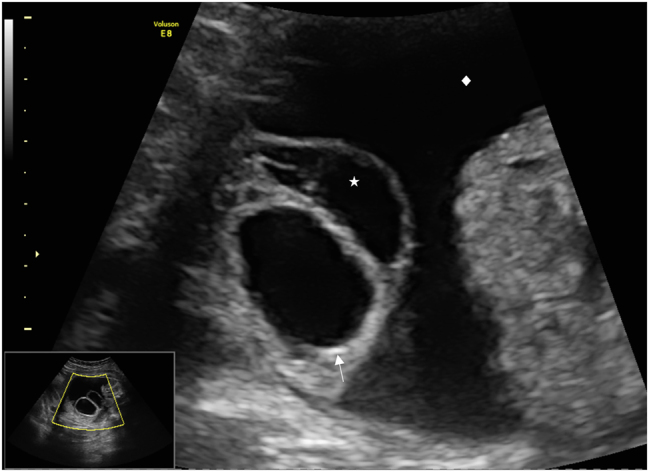

Case presentation: A 18-year old first Gravida at 31 weeks of gestation developed a severe sepsis with progressive hypoxic lung failure and need for intubation. During the ICU-treatment, several opioids were administered for sedation and pain relief. Four days after induction of opioid treatment the ultrasound revealed a decompressed fetal bladder, hematoma and significant ascites. Fetal bladder rupture with urinary ascites was suspected. A caesarean section was performed at 33 weeks of gestation due to massive fetal urinary ascites, fetal deterioration and imminent abdominal compartment syndrome. Adequate ventilation and circulation could only be established after percutaneous drainage of 350 mL of abdominal fluid, that was confirmed to be urine. A defect of the bladder was confirmed by ultrasound. On the fifth day of life, the bladder was closed surgically by pediatric surgery.